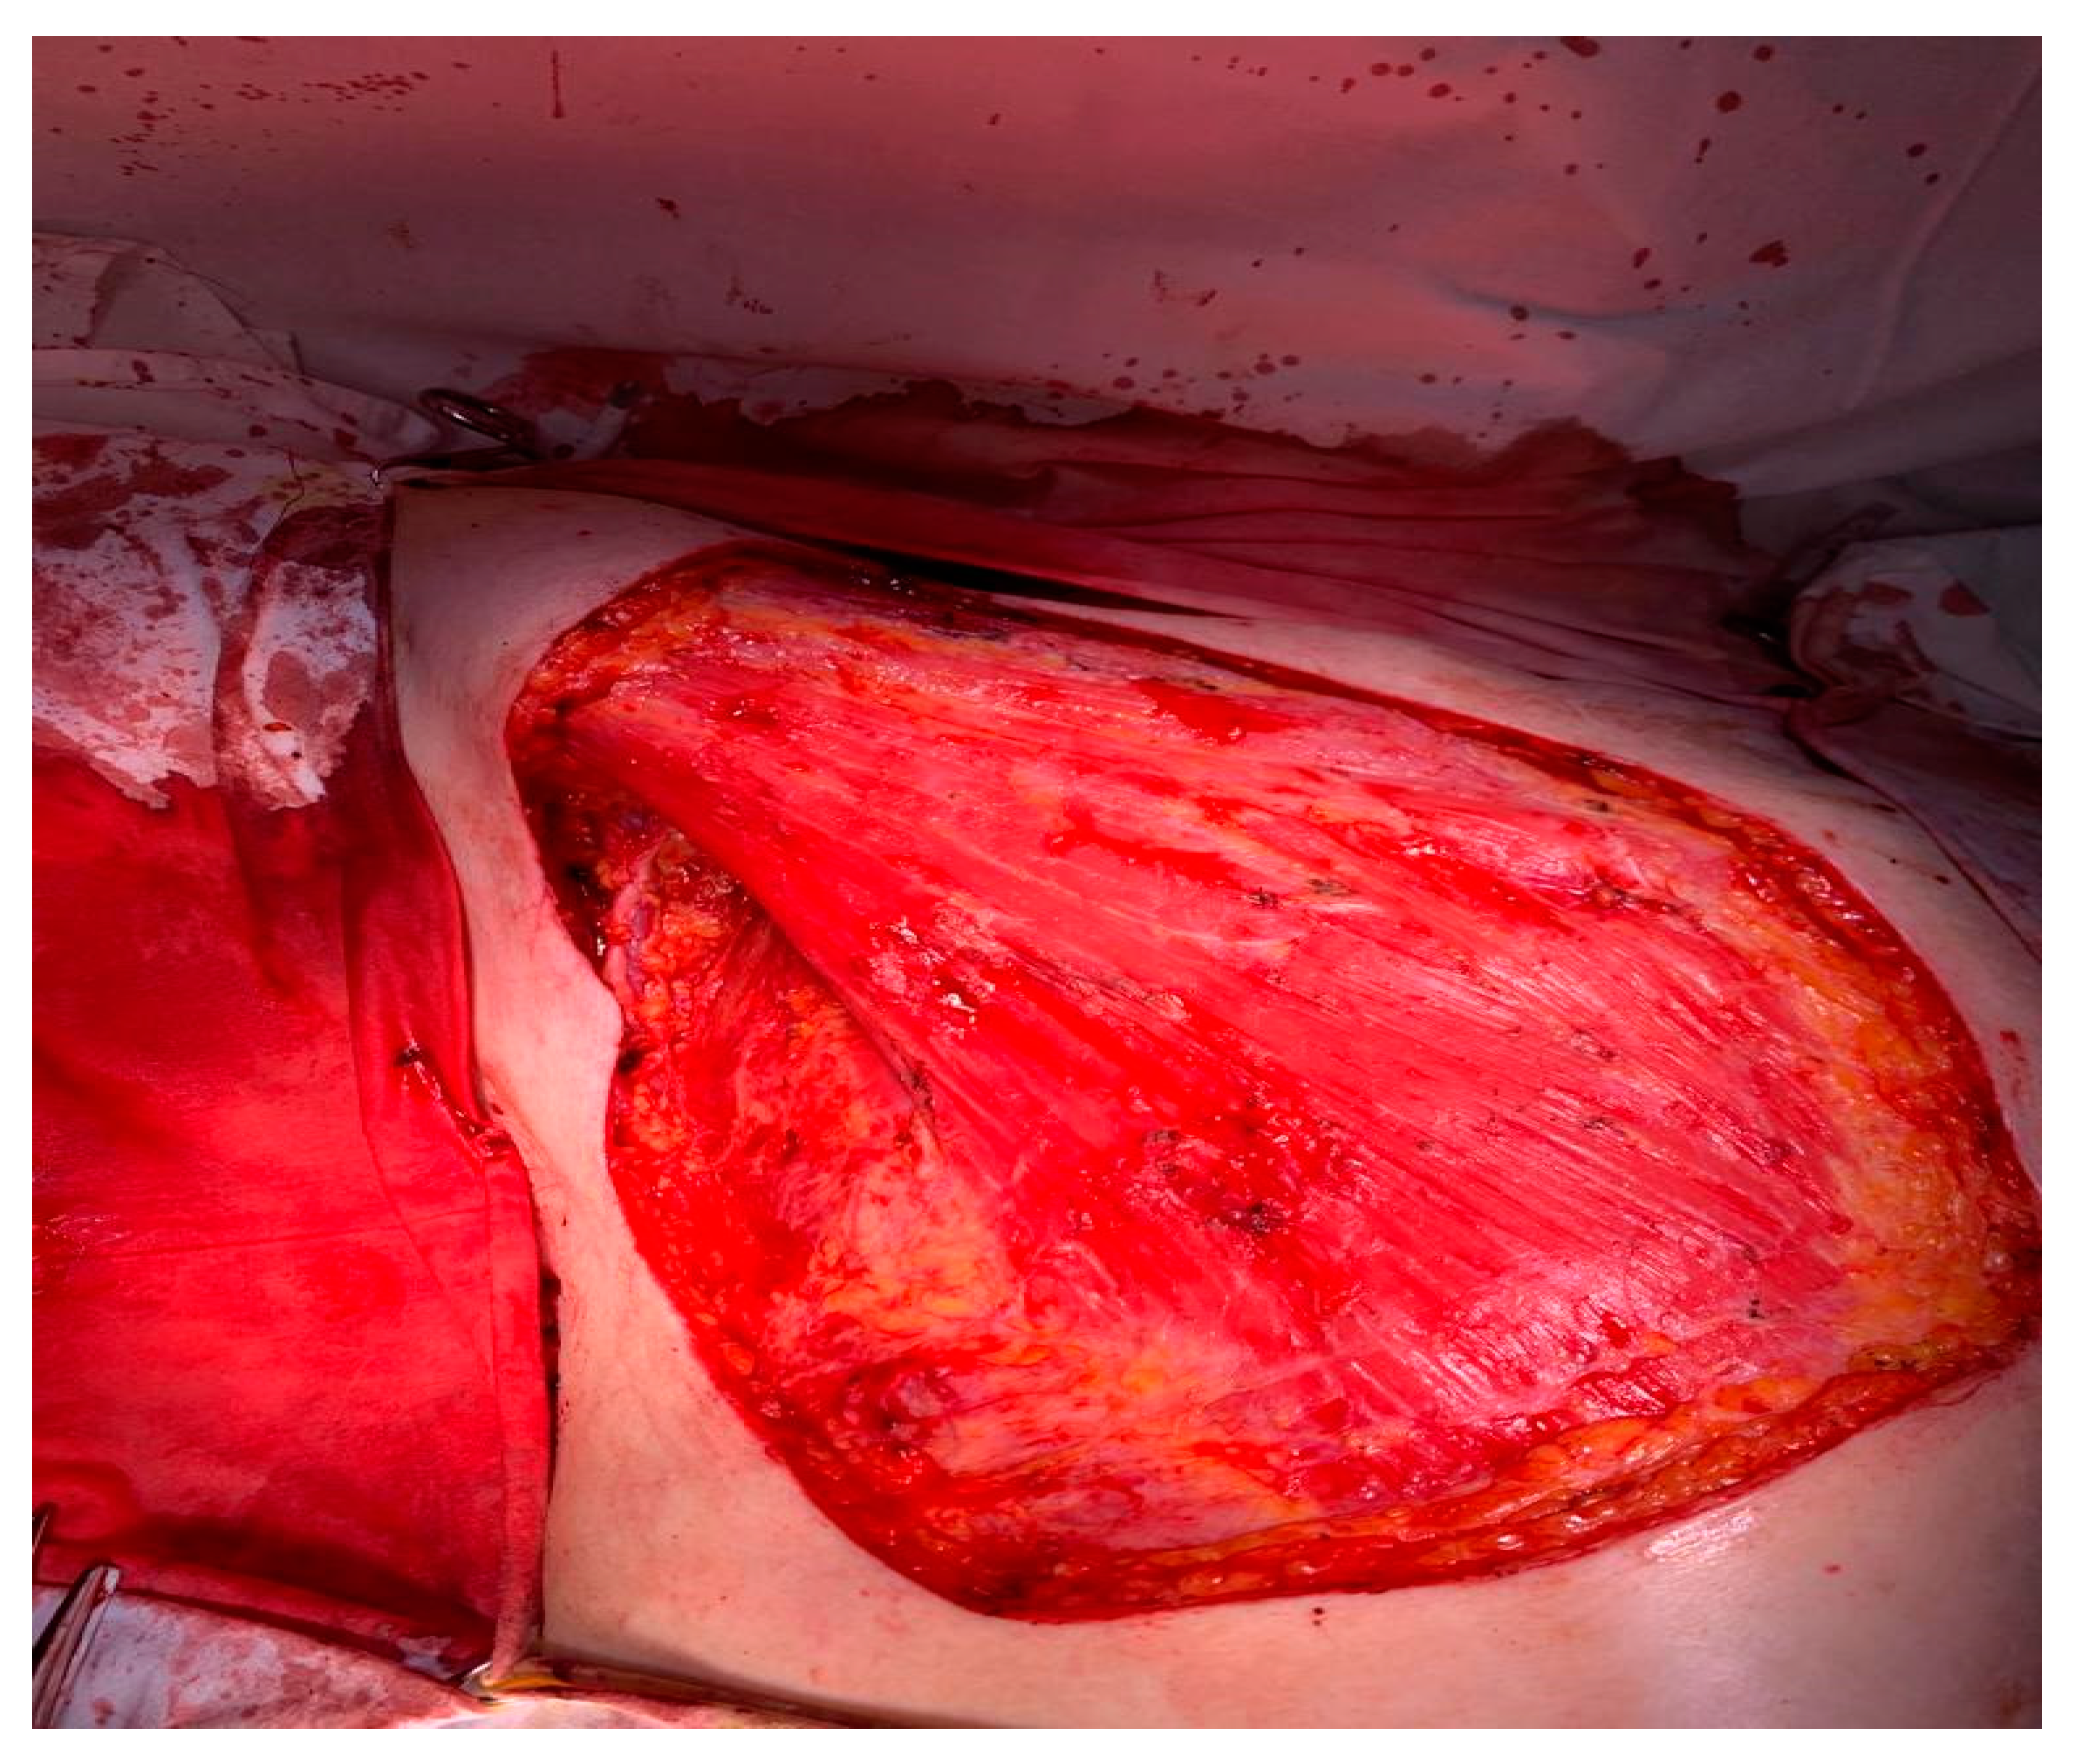

2. Case Presentation